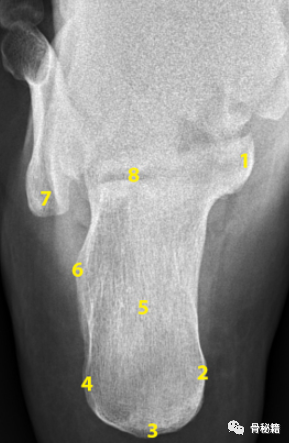

2. 轴位片。主要用于评价跟骨外翻畸形程度、宽度、后关节面的塌陷及与跗骨窦的相对位置。